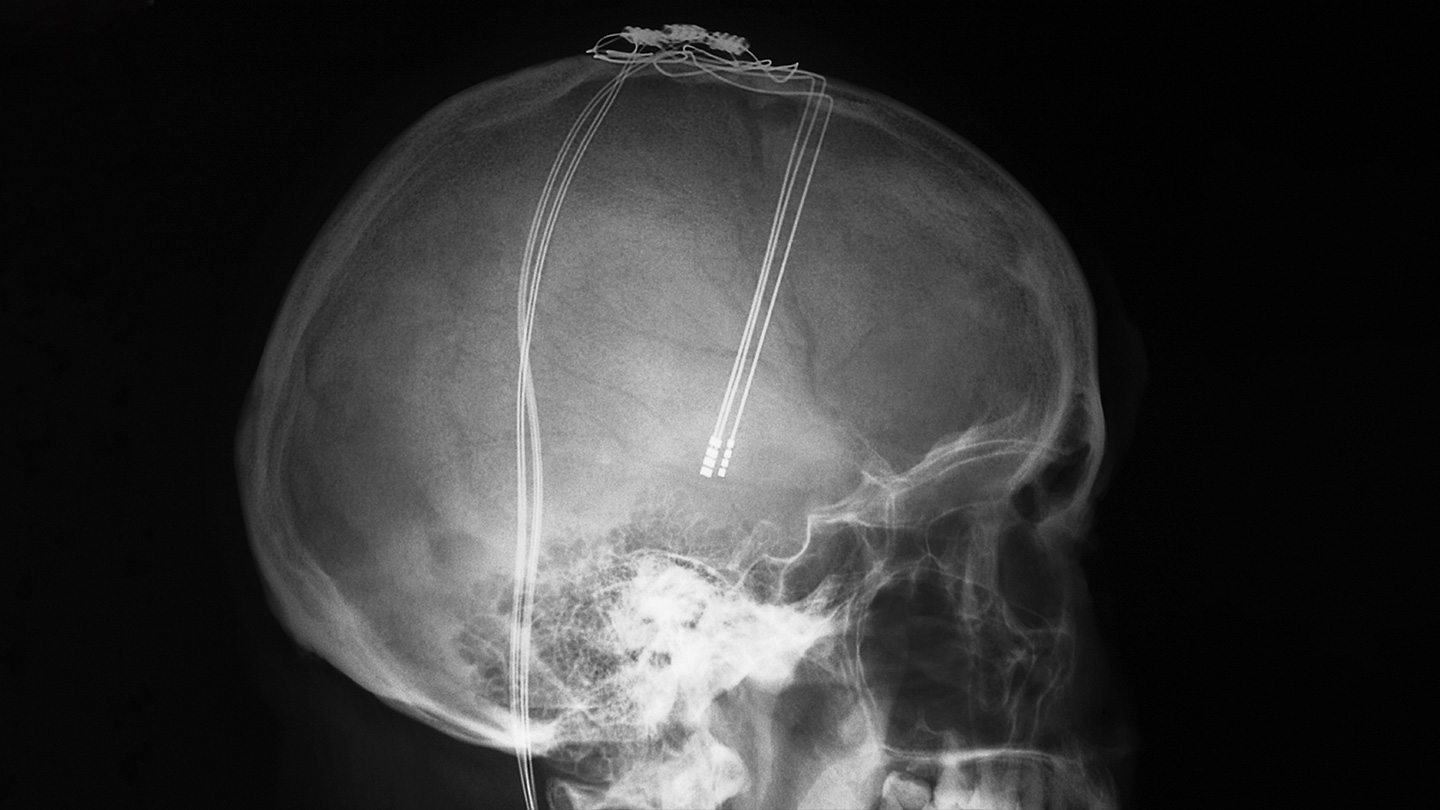

Already, a technique known as deep brain stimulation, or DBS, uses electrodes surgically implanted in people’s brains to tweak the behavior of brain cells. Such electrode implants are helping reduce Parkinson’s tremors, epileptic seizures and uncontrollable movements caused by Tourette’s syndrome. Mood disorders like Sarah’s have been targeted too.

Compared with those early days, today’s scientists understand a lot more about how to selectively influence brain activity. But before a treatment such as Sarah’s is possible, two major challenges must be addressed: Doctors need better tools — nimble and powerful systems that are durable enough to work consistently inside the brain for years — and they need to know where in the brain to target the treatment. That location differs among disorders, and even among people.